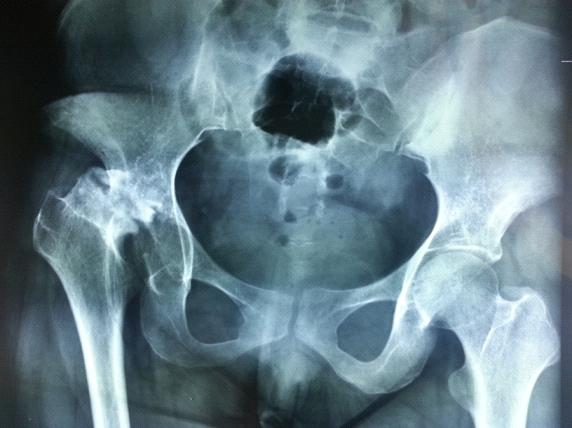

術(shù)前平片 術(shù)后平片

患者女性31歲,住院號(hào)1507226,因右髖關(guān)節(jié)活動(dòng)受限僵硬跛行4年入院,患者4年前患右髖關(guān)節(jié)結(jié)核在我院接受手術(shù),由于結(jié)核嚴(yán)重破壞股骨頭和髖臼,術(shù)后結(jié)核病灶雖得到痊愈但髖關(guān)節(jié)結(jié)構(gòu)完全缺失,出現(xiàn)髖關(guān)節(jié)病理脫位并融合,造成患肢短縮達(dá)8cm,髖關(guān)節(jié)僵硬嚴(yán)重跛行生活自理困難。入院后經(jīng)系列檢查發(fā)現(xiàn)患髖關(guān)節(jié)股骨頭缺失,股骨頸殘端上移異位融合,髖臼缺損平坦,由于股骨上移,股血管和神經(jīng)伴隨移位,髖關(guān)節(jié)周?chē)馄十惓?,加之關(guān)節(jié)病理融合廣泛疤痕粘連,要完成髖關(guān)節(jié)置換手術(shù)不僅需要重建髖臼,還要松解關(guān)節(jié)恢復(fù)下肢長(zhǎng)度,才能達(dá)到術(shù)后雙下肢等長(zhǎng)目的,手術(shù)難度極高,風(fēng)險(xiǎn)極大。在骨科主任、主任醫(yī)師田建洪帶領(lǐng)下,經(jīng)過(guò)認(rèn)真研究,大膽設(shè)計(jì),決定采用先進(jìn)3D技術(shù)將患髖關(guān)節(jié)異常病理結(jié)構(gòu)按1:1比例實(shí)體打印復(fù)制呈型,為手術(shù)醫(yī)師提供術(shù)前立體圖觀,幫助術(shù)者按3D實(shí)體準(zhǔn)確重建髖關(guān)節(jié)結(jié)構(gòu)并立體導(dǎo)航手術(shù)解剖。3D技術(shù)應(yīng)用外科手術(shù)是醫(yī)學(xué)領(lǐng)域的重大突破,目前僅少數(shù)醫(yī)院開(kāi)展,我院在2015年9月7日成功施行該例手術(shù),目前患者已康復(fù)出院,此例手術(shù)的成功,標(biāo)志我院骨科在脊柱結(jié)核手術(shù)省內(nèi)領(lǐng)先的基礎(chǔ)上又將3D技術(shù)應(yīng)用于髖關(guān)節(jié)結(jié)核人工關(guān)節(jié)置換高難度手術(shù)上了新臺(tái)階。

討論:髖關(guān)節(jié)結(jié)核好發(fā)于中青年,男性多于女性,髖關(guān)節(jié)結(jié)核除了體內(nèi)原發(fā)病灶通過(guò)血或淋巴等途經(jīng)感染髖關(guān)節(jié)外,尚可因髖臼外方的髂骨結(jié)核大轉(zhuǎn)子結(jié)核,后方骶髂關(guān)節(jié)結(jié)核等蔓延至髖關(guān)節(jié),此外脊柱結(jié)核亦可通過(guò)腰大肌膿腫流注至髂恥束而引發(fā)髖關(guān)節(jié)結(jié)核。髖關(guān)節(jié)結(jié)核通常發(fā)病緩慢,全身中毒癥狀不顯著,疼痛是髖關(guān)節(jié)結(jié)核最先出現(xiàn)的癥狀,初時(shí)疼痛多不甚明顯,休息后及可減輕,少數(shù)急驟發(fā)病的髖關(guān)節(jié)結(jié)核可有劇烈疼痛和關(guān)節(jié)活動(dòng)受限,大多數(shù)病人早期癥狀不重,不重視,誤診、誤治,隨著病情的發(fā)展出現(xiàn)關(guān)節(jié)功能障礙,本患者4年前診斷“髖關(guān)節(jié)結(jié)核”,入院時(shí)跛行,股骨頭明顯骨質(zhì)破壞,經(jīng)規(guī)則結(jié)核化療3周后行手術(shù)治療,術(shù)后繼續(xù)規(guī)則結(jié)核化療18月,結(jié)核痊愈,但患者關(guān)節(jié)功能?chē)?yán)重受影響,關(guān)節(jié)周?chē)∪鈹伩s,導(dǎo)致患肢上移,縮短,股骨頭缺失,股骨頸殘端上移異位融合,假關(guān)節(jié)形成,術(shù)前采用3D技術(shù)將患髖關(guān)節(jié)按1:1比例實(shí)體打印復(fù)制呈型,術(shù)中充分松解髖關(guān)節(jié)周?chē)∪猓眯√?hào)人工假體置入并松解關(guān)節(jié)周?chē)鷶伩s肌肉組織,將人工關(guān)節(jié)復(fù)位檢查髖關(guān)節(jié)各方向活動(dòng)無(wú)阻礙,術(shù)后患者雙下肢基本等長(zhǎng),步態(tài)正常,手術(shù)取得滿意效果。